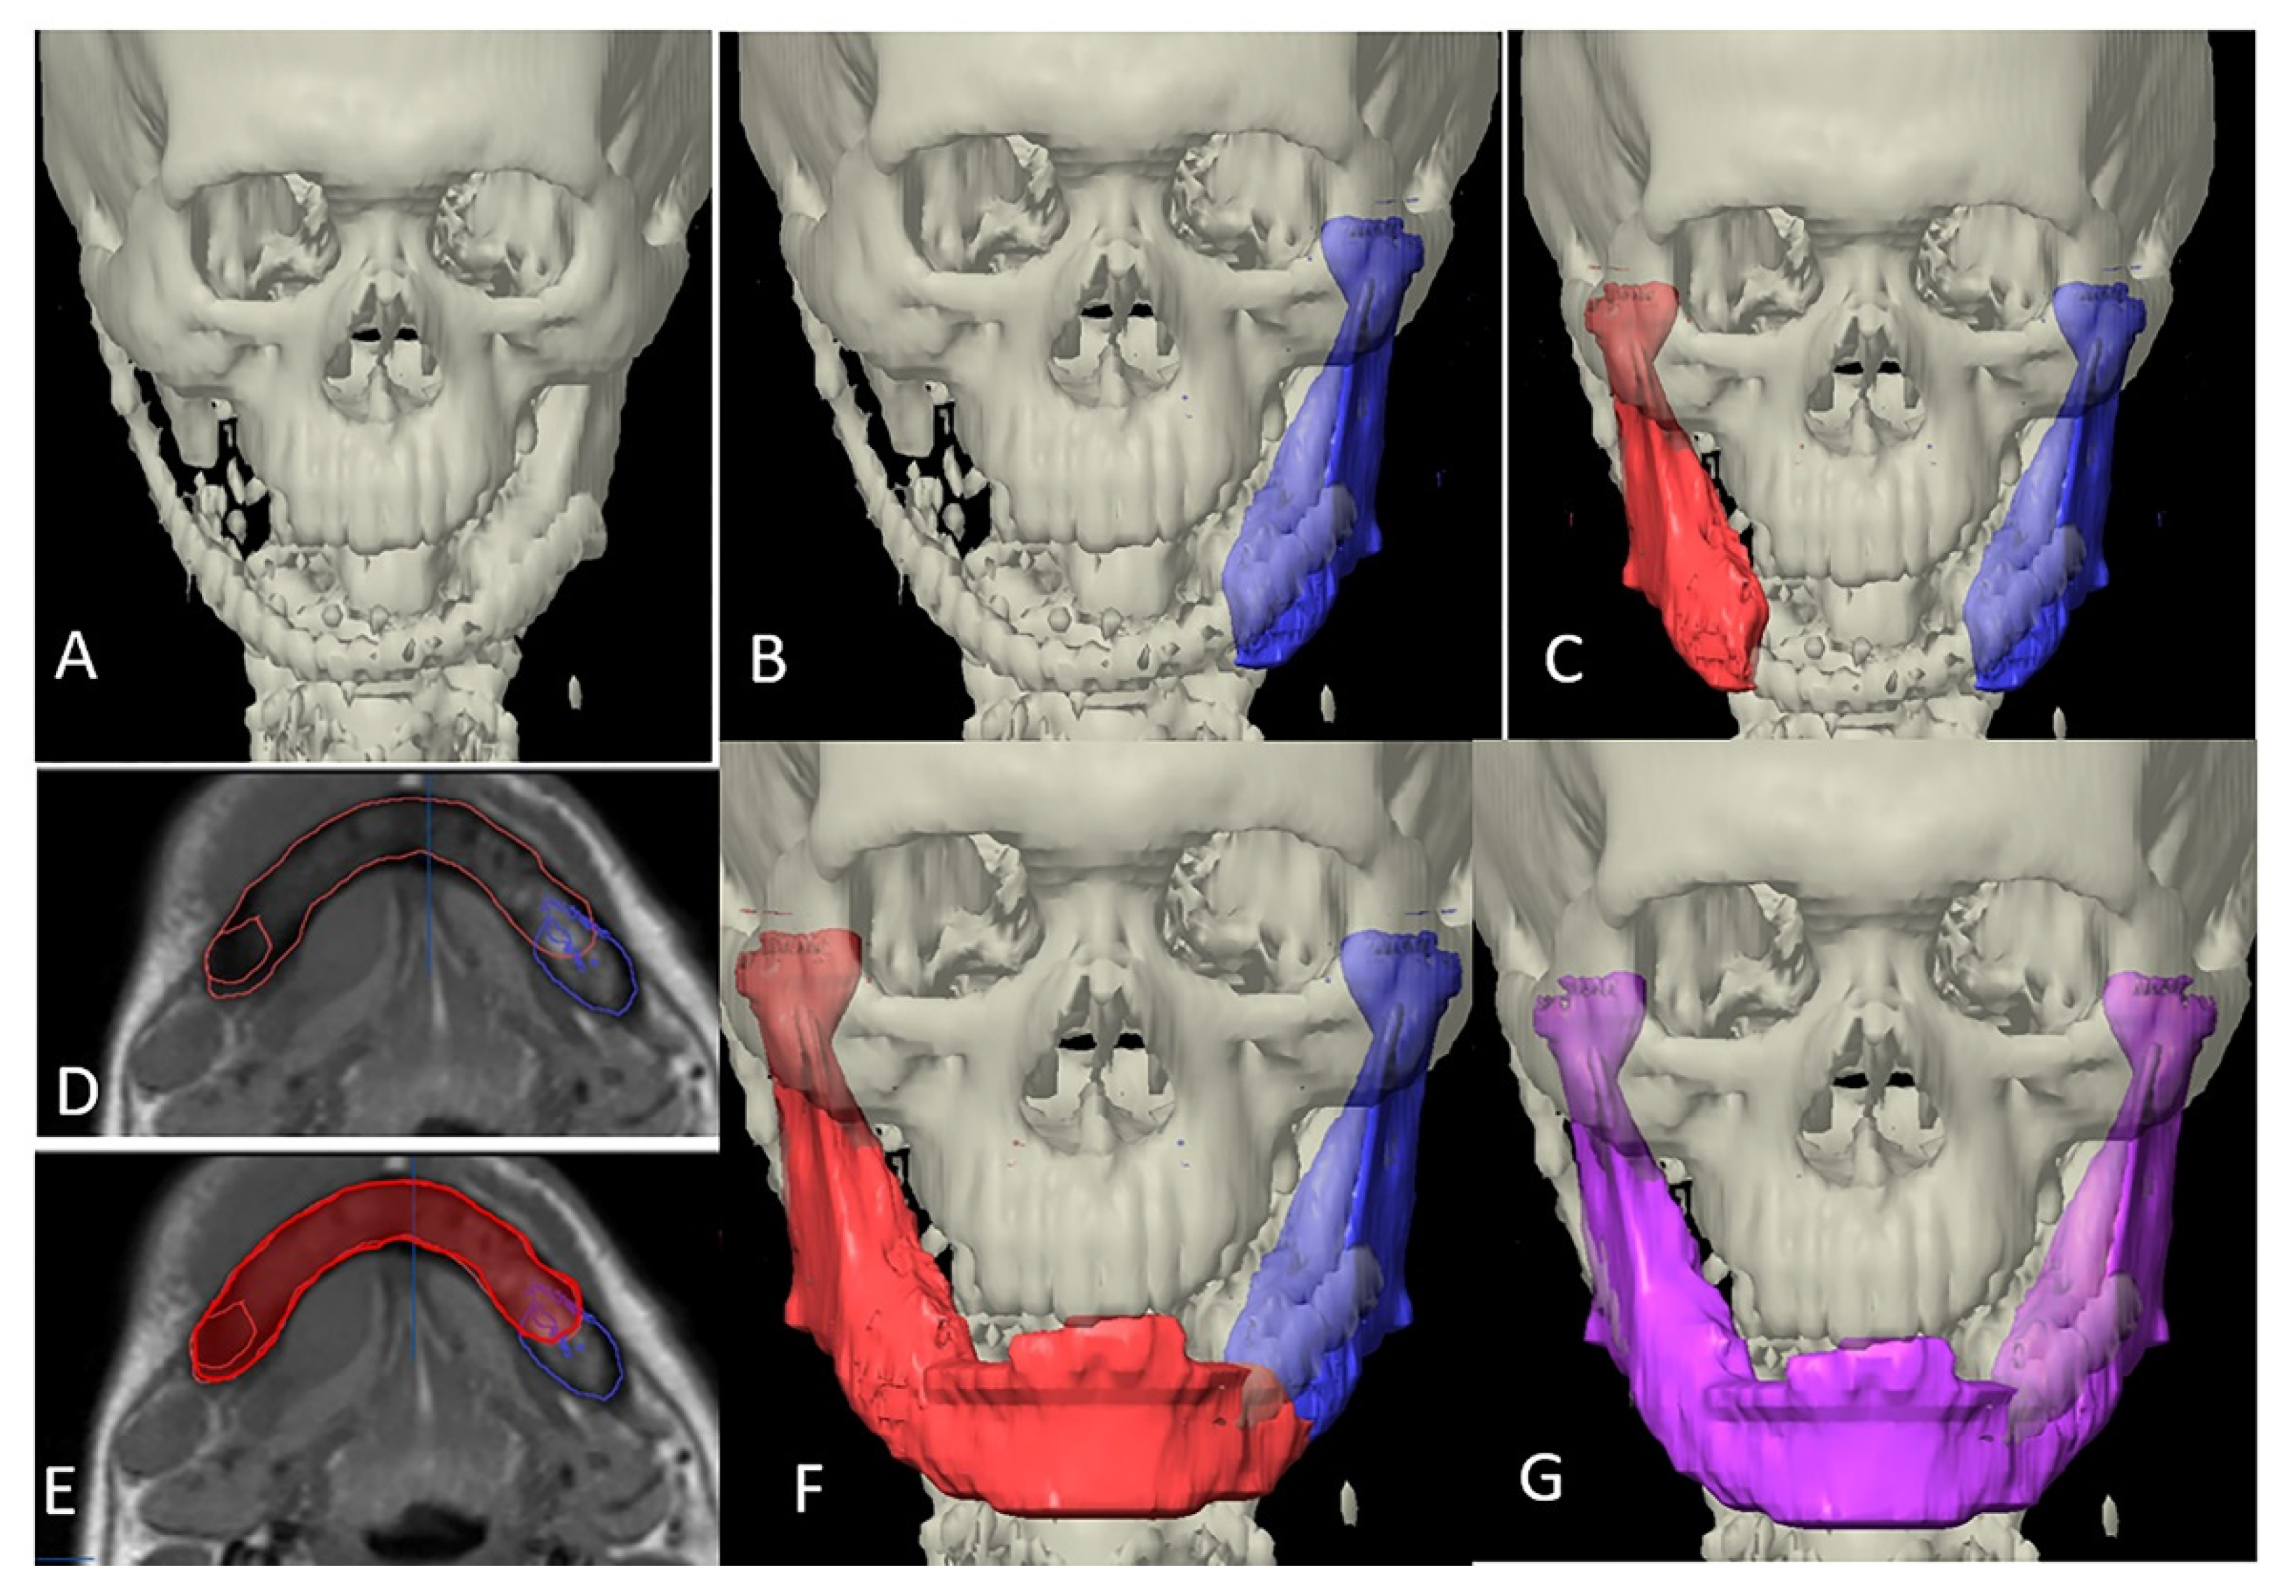

In category II, the ablative defect extended past the midline. CT/MRI taken before the primary surgery were superimposed over the postoperative/current imaging, necessary realignment of the residual segment was carried out and then mirrored. The unresected portion from the previous imaging was then used as template to manually delineate the mandibular contour to reproduce a whole mandible (Figure 3).

Figure 3.

Designing template in category II. (A) 3-dimensional view of defect. (B) Segmentation of the remaining mandible on the left side (blue color). (C) Mirroring to the right side (red color). (D) Superimposing the current CT scan axial view to previous MRI. (E) Drawing the residual defect (red). (F) 3-dimensional view of virtually reconstructed defect (red). (G) Merging the segmented part, mirrored part and drawn part to form whole simulated mandible for printing (purple color).